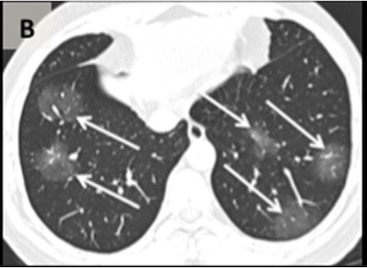

Le temps entre l'apparition initiale des symptômes et la TDM thoracique était connu pour 94 patients et estimé comme précoce (0-2 jours), intermédiaire (3-5 jours) ou tardif (6-12 jours). La fréquence des opacités et de la consolidation

du verre dépoli était bien moindre dans le groupe précoce par rapport aux groupes intermédiaire et tardif. Une atteinte pulmonaire bilatérale a été observée chez 10 des 36 patients précoces (28%), 25 des 33 patients intermédiaires (76%) et 22 des 25 patients en retard (88%). Les opacités linéaires, un motif de pavage fou » et un signe de « halo inversé » étaient tous absents dans le premier groupe, mais étaient présents dans le dernier groupe. D’autre part, une distribution périphérique a été trouvée chez 8 des 36 patients précoces (22%), 21 des 33 patients intermédiaires (64%) et 18 des 25 des patients tardifs (72%).